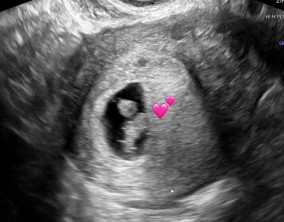

심장소리 이후, 함께 웃게 된 임밍아웃

유정원장님 치료 과정 내내 항상 따뜻하게 진료해 주셔서 감사한 마음이 큽니다. 덕분에 불안한 순간에도 마음을 다잡고 치료를 이어갈 수 있었습니다.